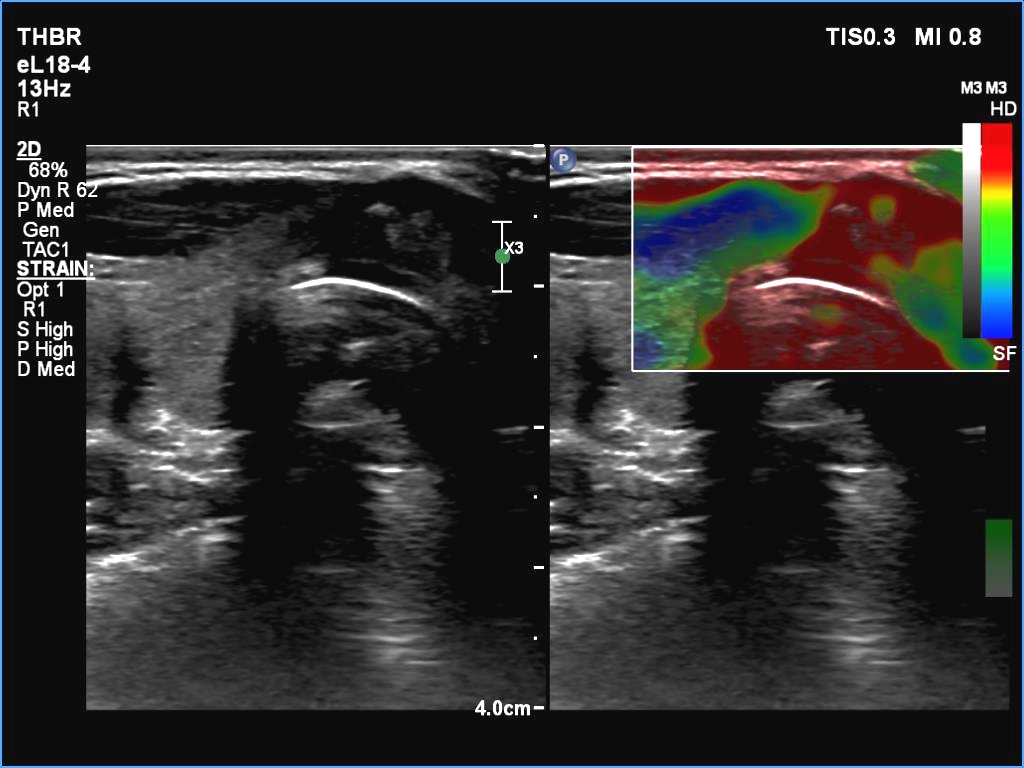

Right lobe, longitudinal scan

Isthmus, transverse scan, elastography. This is a non-secific, difficult-to-evaluate pattern.